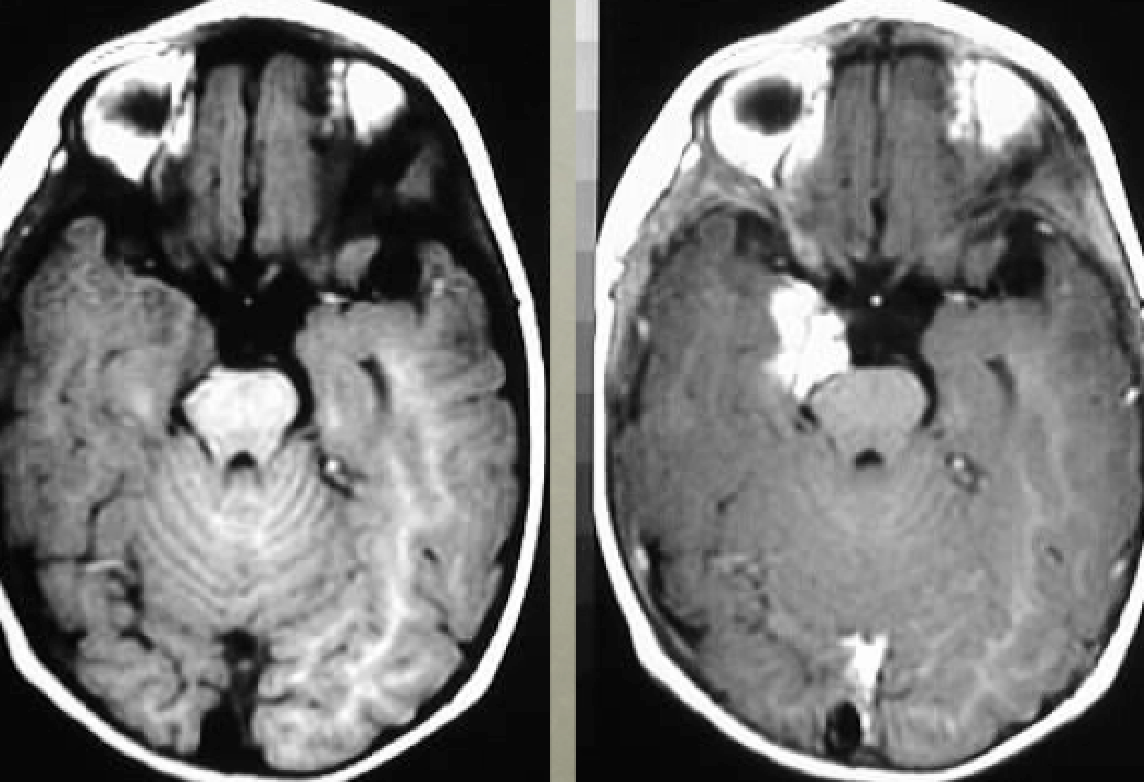

5yo with ataxia, vomiting, and headache

Differential diagnoses and most likely diagnosis?

Differential:

Ependymoma

Juvenile pilocytic astrocytoma

Medulloblastoma.

Most likely:

Ependymoma - 4th ventricle mass, expanding through Magendie and Luschka foramina. Can calcify and have cystic components. Nonhomogeneous contrast enhancement.